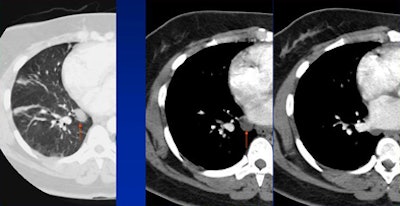

|  |

| False-positive: Loculated pericardial fluid is often misread as a lung mass. |